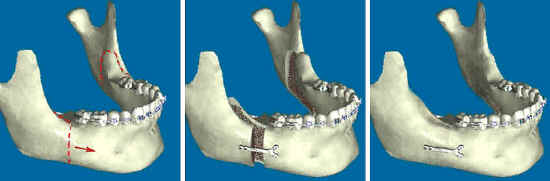

BSSO là từ viết tắt của từ Bilateral Sagittal Split Osteotomy nghĩa là cắt cành bên hai xương hàm dưới rồi đẩy lùi về phía sau. Ưu điểm của phẫu thuật này là không cần nhổ răng, điều trị triệt để các trường hợp móm quá mức hay gọi là hàm cắn ngược hoặc vẩu hàm dưới.

Phương pháp cắt xương hàm BSSO mang lại hiệu quả cao trong phẫu thuật chỉnh hình xương hàm trị móm qua một lần phẫu thuật duy nhất, làm cho gương mặt trở nên hài hòa và nụ cười duyên dáng hơn.

Bác sĩ tiến hành kỹ thuật BSSO cắt xương hàm dưới đẩy lùi về sau kèm cắt xương hàm trên đẩy trượt về trước sau đó nẹp cố định hàm.